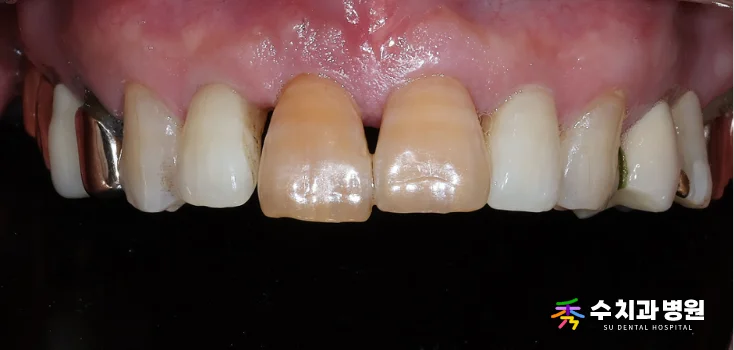

🔍 치료 전 (Before)

[치료 전 사진] (촬영일: 2025년 06월)

환자분은 앞니 하나가

점점 아래로 처지는 느낌이 들어

걱정스러운 마음에 내원하셨습니다.

정밀 검사 결과, 오른쪽 대문니(앞니)는

과거에 신경치료를 받았던 이력이 있었습니다.

뿌리 쪽 잇몸뼈 흡수가 심하게 진행되어

치아가 제 위치를 잡지 못하고 있었습니다.

치아가 심하게 흔들리는 상태였기 때문에

안타깝게도 발치가 불가피했습니다.

또한 옆 치아의 색상도 변색이 진행되어

심미적인 개선이 시급했습니다.